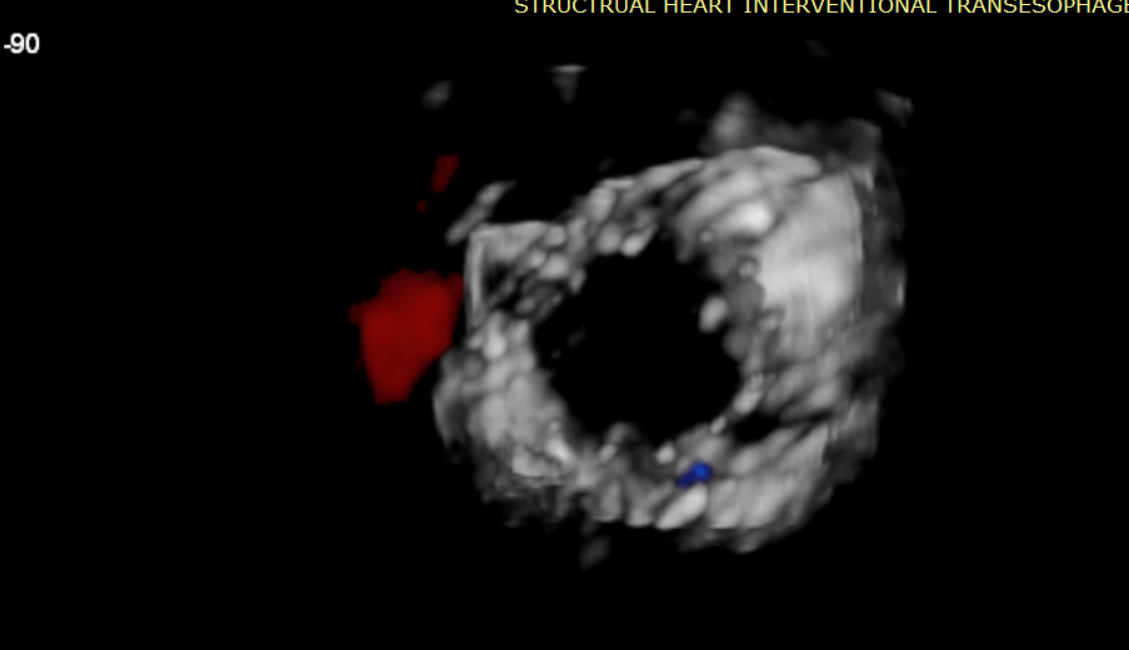

經(jīng)過Azeem Latib教授帶領(lǐng)的多學科團隊討論,本次接受治療的兩位患者均為外科手術(shù)高危;且受限于影像和解剖結(jié)構(gòu)的局限性,其他的經(jīng)導(dǎo)管修復(fù)、置換系統(tǒng)均不適用。而LuX-Valve Plus獨特的錨定機制(即脫離徑向支撐力的“室間隔錨定”設(shè)計理念)和對術(shù)中超聲影像的低要求,使得Azeem Latib教授團隊認為這一中國創(chuàng)新醫(yī)療器械可以對這兩名患者進行有效治療。

術(shù)后Azeem Latib教授對LuX-Valve Plus經(jīng)血管三尖瓣置換系統(tǒng)的器械性能和治療效果大為稱贊,并且認為LuX-Valve Plus的手術(shù)體驗非常好。從治療效果來看,術(shù)后即刻超聲顯示三尖瓣反流幾乎完全消失,血流動力學改善顯著,患者恢復(fù)快。在面對復(fù)雜解剖結(jié)構(gòu)、超聲影像質(zhì)量不佳、有起搏導(dǎo)線干擾時,Lux-Valve Plus也體現(xiàn)了極強的適應(yīng)性。Thomas Modine教授參與了術(shù)中指導(dǎo),他同樣再次肯定了LuX-Valve Plus術(shù)中操作的便捷性,認為LuX-Valve Plus容錯率高,對術(shù)中影像的依賴小,并表達了后期希望可以更多地應(yīng)用LuX-Valve Plus三尖瓣置換系統(tǒng)于臨床實踐,讓更多的三尖瓣重度反流患者盡早獲益,改善預(yù)后。